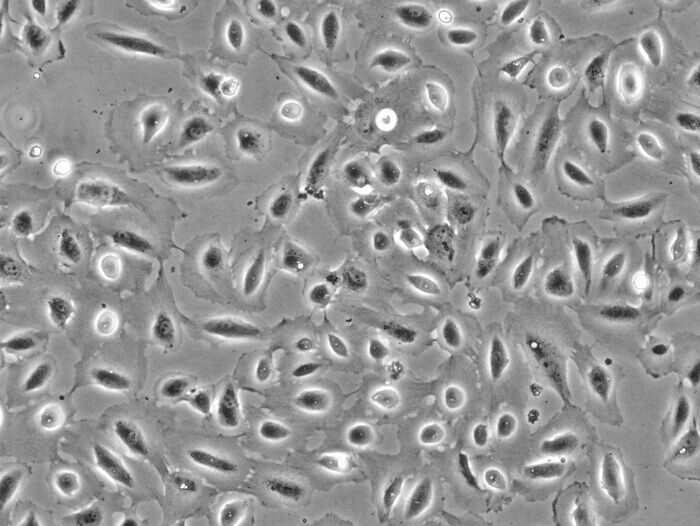

细胞形态:悬浮

Jurkat细胞(人外周血白血病T细胞),是一种悬浮细胞。我的经验如下:1、培养液:RPMI1640,15%小牛血清,2%Na2CO3,1%HEPES,青霉素100IU/1ml,庆大霉素100IU/ml;2、培养条件:5%CO2,37度,30%湿度;3、细胞复苏:要快速将冻存管放入37度水中,不断轻轻摇晃,直到细胞完全溶解,加入10ml左右的培养液,800~1000rpm,10分钟离心,之后倒掉液体,加入新的培养基就可以进行培养了;4、细胞培养:起初进行传代时由于细胞刚刚复苏,长得比较